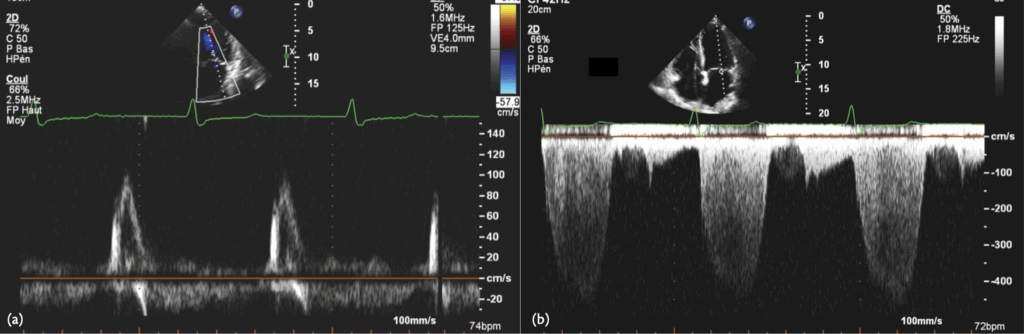

A 72-year-old patient was implanted with a dual-chamber pacemaker for sick sinus syndrome, programmed with the ADIR/DDDR algorithm. His LVEF was normal. The device counters indicated 96% AP and 2% VP. He complained of persistent dyspnoea. A real-time EGM is shown & transthoracic echocardiogram was performed, and the transmitral Doppler flow is shown here

P on T’

The ADI/DDD algorithm tolerates very long AVIs, which may, as in this case, lead to ‘P on T’, with atrial contraction occurring during ventricular systole, as in the pacemaker syndrome. The detrimental haemodynamic effect of RV pacing in the DDD mode needs to be balanced against improved AV synchrony. In this case, programming the pacemaker to the DDD mode revealed improved ventricular filling (below), with the appearance of an A-wave, as seen below. Also, diastolic mitral regurgitation was eliminated, although it probably was not the main cause of the patient’s symptoms.